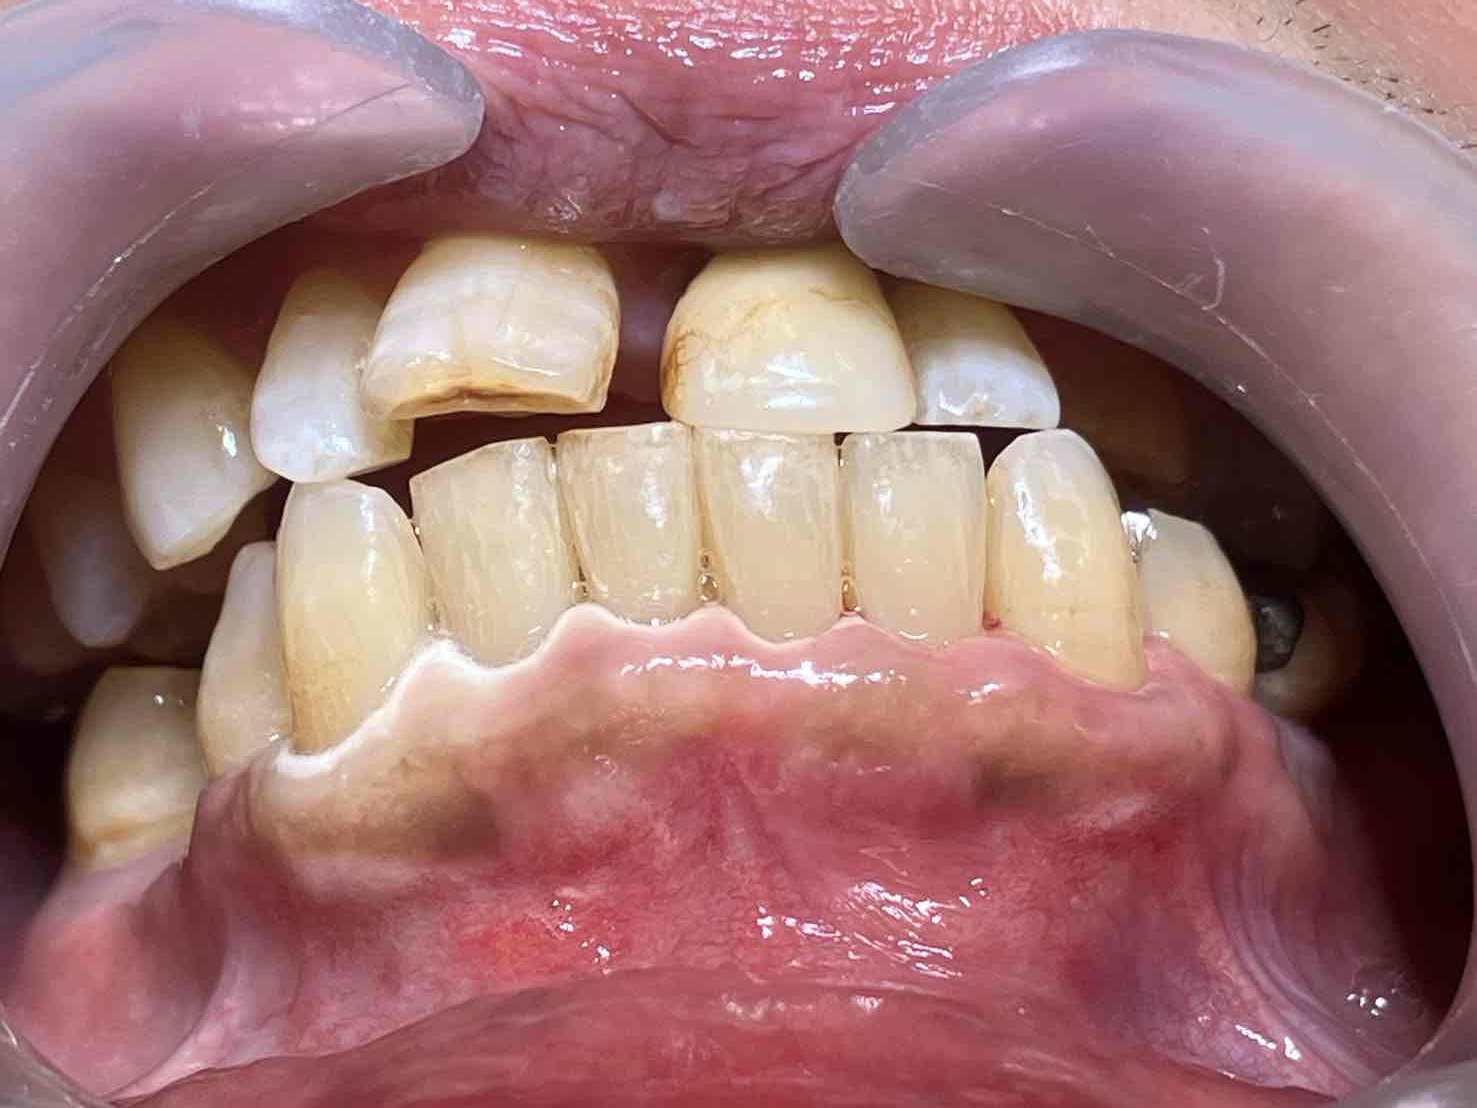

“実際の施術例2”

この患者様は、スケーリングより歯周ポケットが6mm以上ある患者様で患者様ご本人も歯周病になりかけている自覚がありました。

また、口臭も気になされていましたので、ブルーラジカルの適用症例と判断し、施術を行いました。

(照射前)

施術前のレントゲンと口腔内写真です。